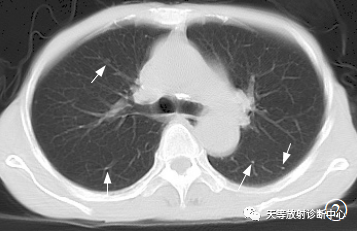

病例2,男,57岁,硬皮症2年

图CT平扫沿支气管血管束散在小结节状影,边界较清;